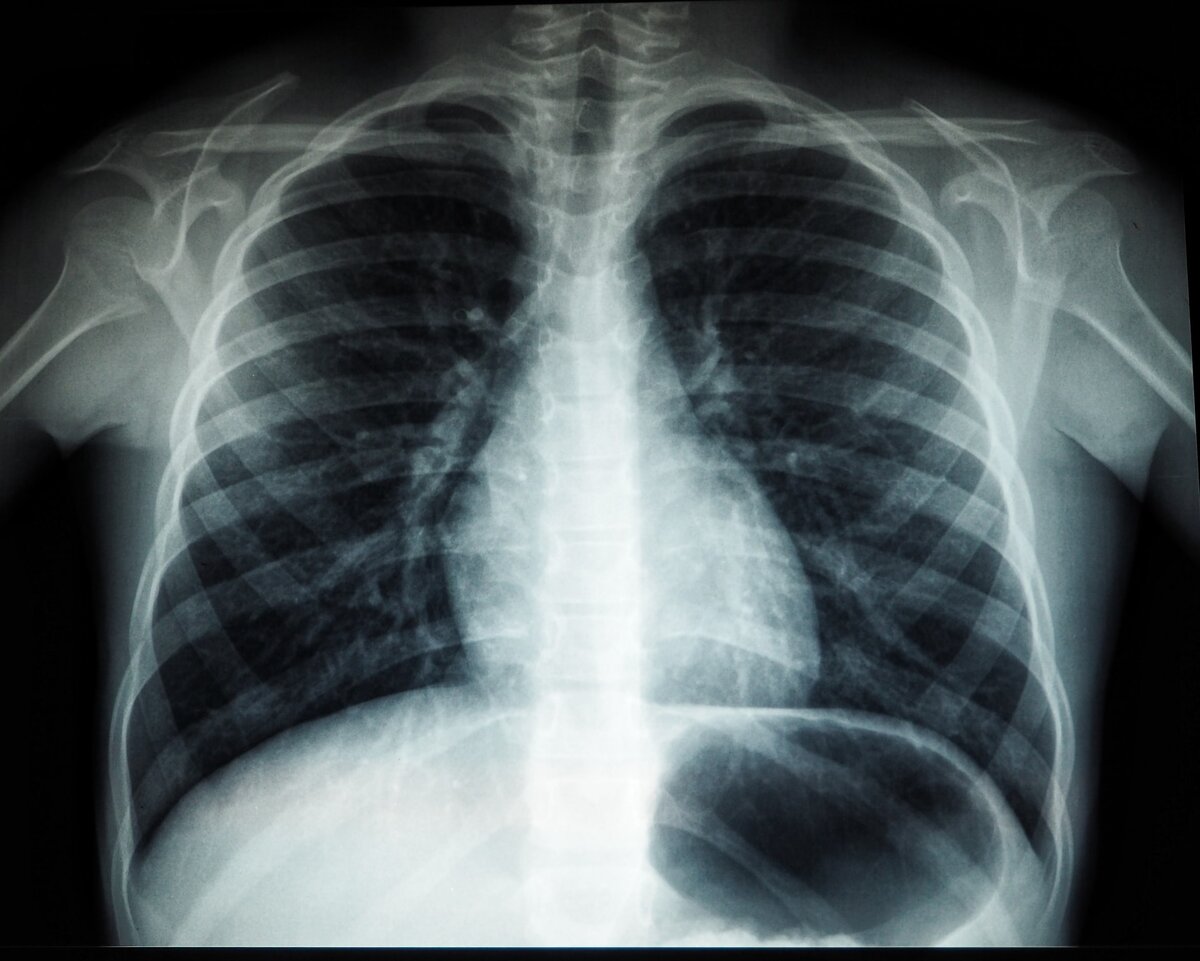

Мы все знаем, что курение в большинстве случаев является основной причиной рака легких. Однако существуют люди, которые могут курить всю жизнь, но они избегают рака. Почему так происходит?

Исследование, проведенное учеными Медицинского колледжа Альберта Эйнштейна, США, предполагает, что у некоторых курильщиков могут быть надежные механизмы, которые защищают их от рака легких. Авторы работы говорят, что дальнейшее изучение таких людей может оказаться “важным шагом на пути к профилактике и раннему выявлению риска рака легких”.